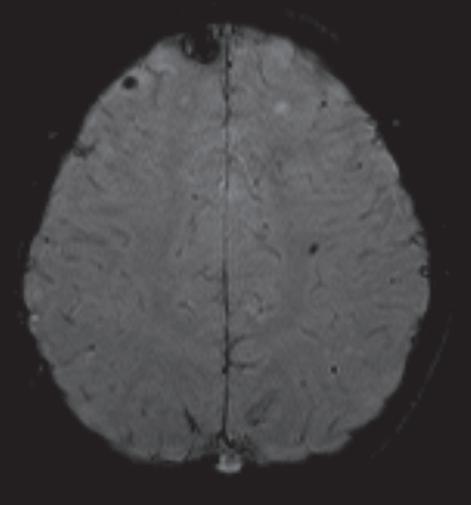

La exploración fue realizada con resonador magnético de alto campo, (1.5 Tesla), Siemens SPREE en cortes axiales, sagitales y coronales, en secuencias ponderadas en T1, T2, FLAIR, Difusión (DW), susceptibilidad (SWI) con la administración de contraste endovenoso paramagnético, fase angiográfica y espectroscopía.

Secuencia de SWI 3D evidencia múltiples imágenes hipointensas, de formas nodulares, algunas de ellas presentan contornos lobulados, distribuidas en ambos hemisferios cerebrales, sin edema

periférico. Sus diámetros oscilan entre 0,2 y 0,8 cm. (Fig. 2,3,4,). Con el medio de contraste no hay cambios en la intensidad de señal.

Cavernomas múltiples complicados con hematoma intraparenquimatoso frontal derecho, secundario a cavernoma accidentado.